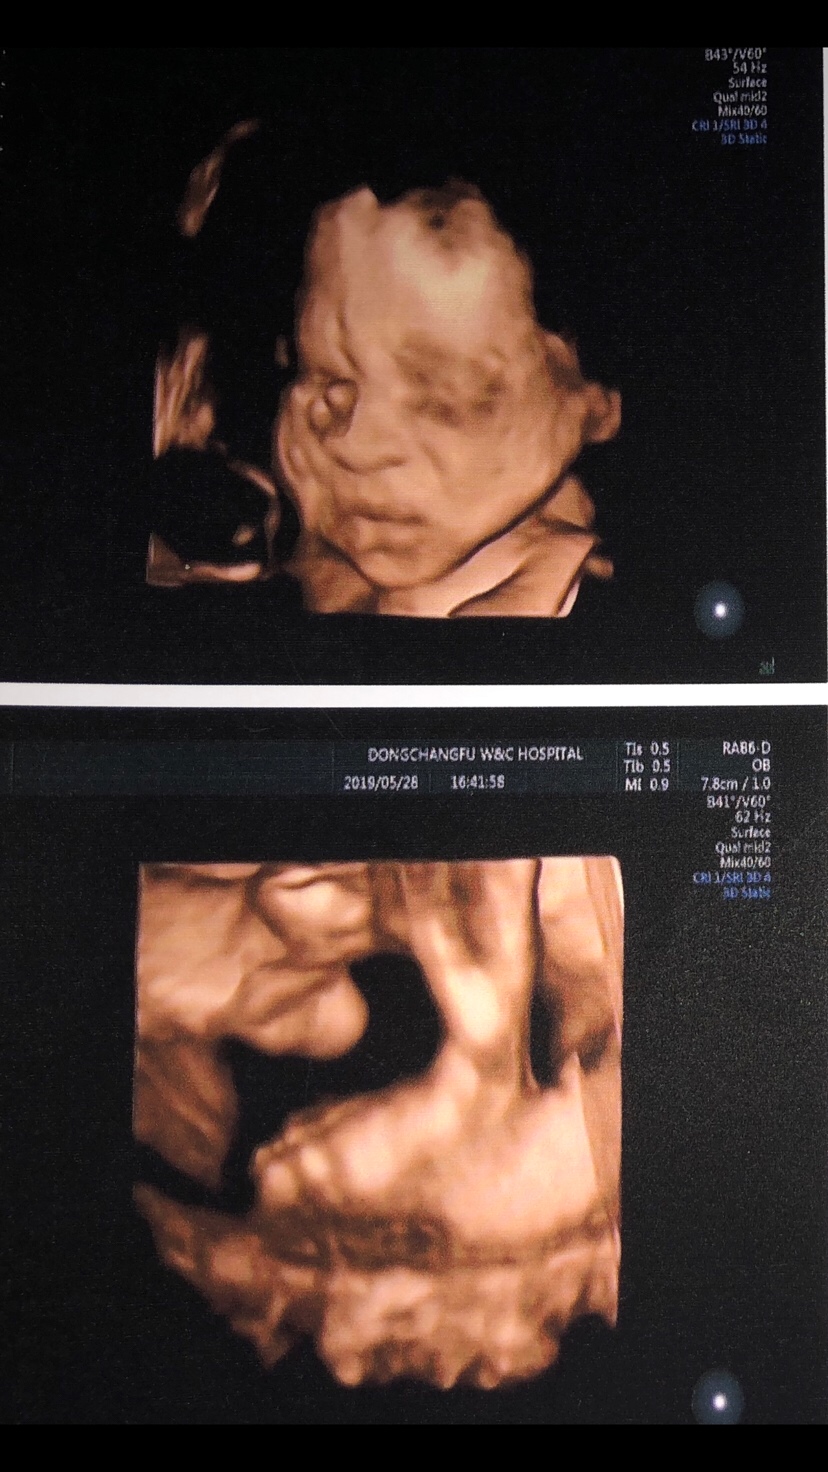

孕34周+1天

恭喜,诚接健康男宝在我腹中🙏🏻🙏🏻🙏🏻